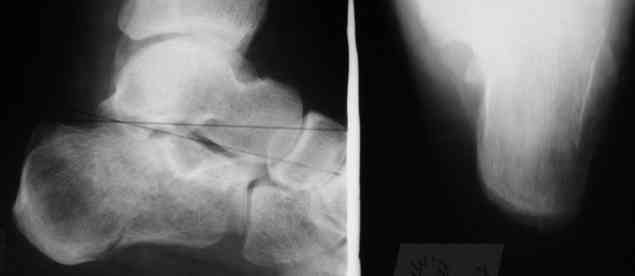

Уважаемые коллеги! Пришел на консультацию больной - "растяжение связок левого голеностопного сустава" полтора месяца назад, поскольку был в морях, на ногу не наступал. Снимки и КТ - в приложении.

Как бы кто лечил с учетом времени после травмы - 52 дня? Человек физического труда. Социальные запросы самого больного высокие, плюс медкомиссии перед рейсами - с хромотой нельзя!